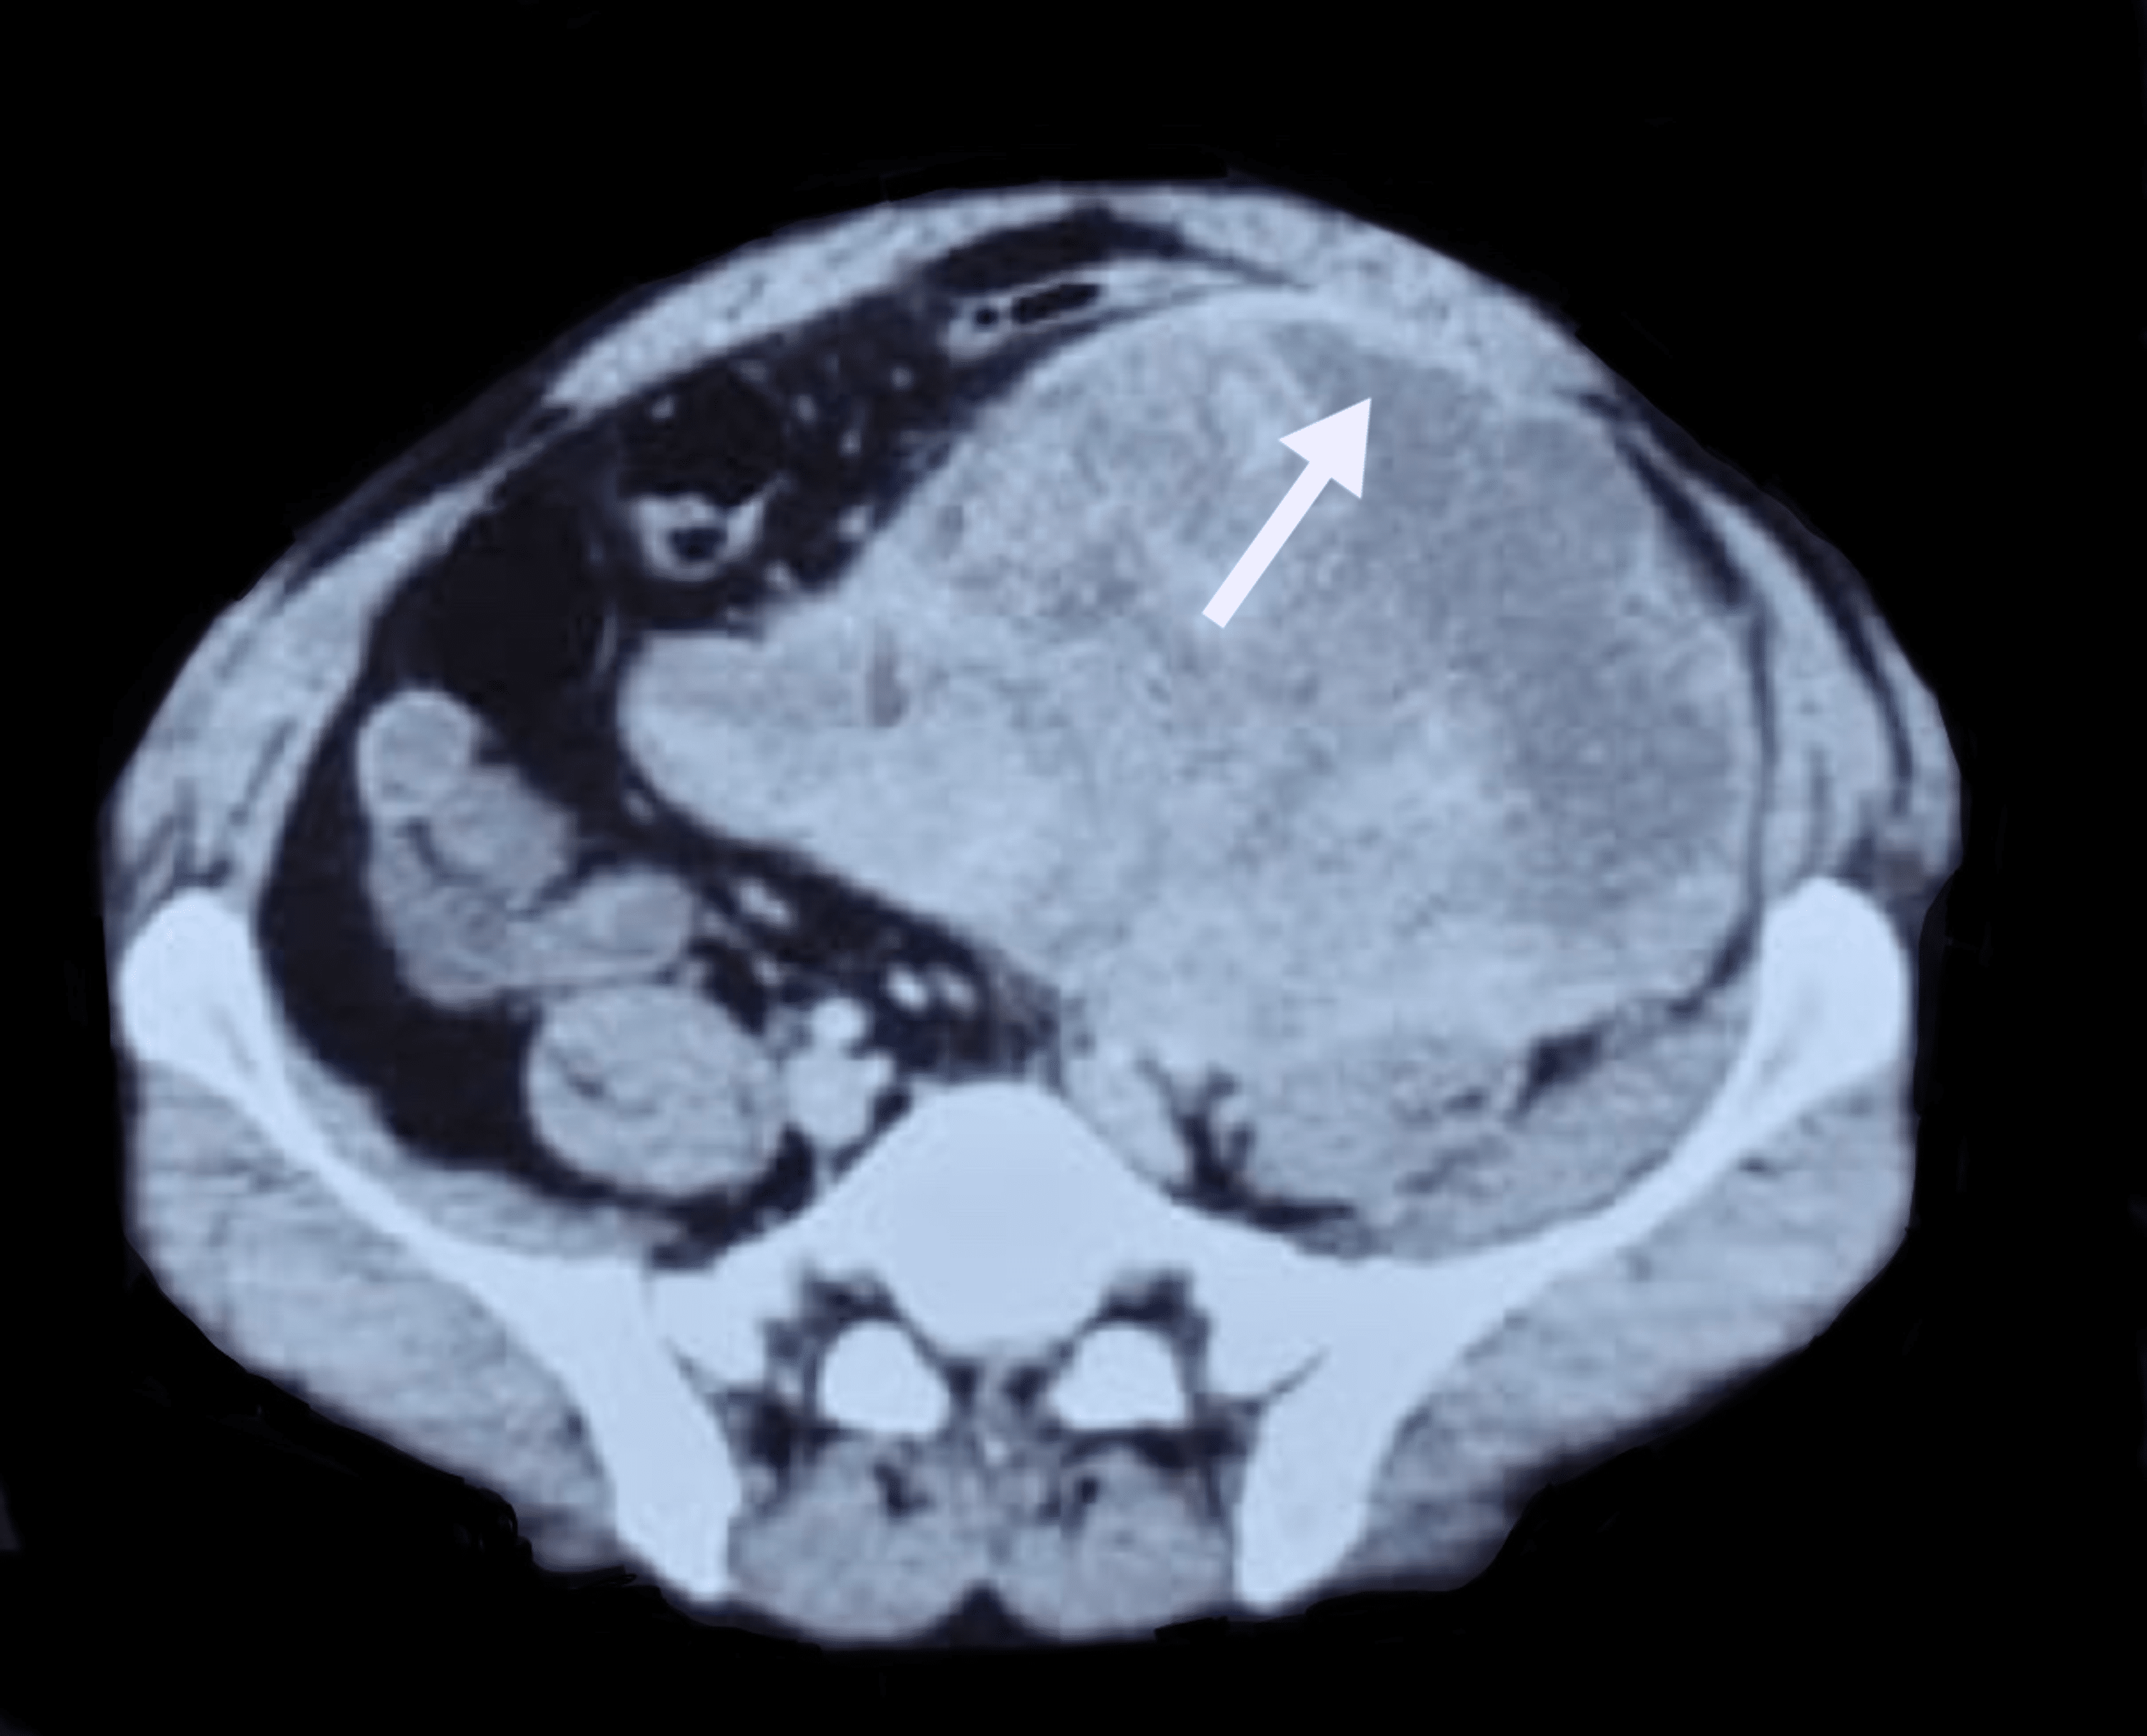

Cureus Retroperitoneal Spindle Cell With Compression Spindle Cell Sarcoma Abdomen It can occur anywhere throughout the body, but it most commonly. An important group of such lesions are the gastrointestinal stromal tumours. Spindle cell sarcoma is a type of undifferentiated sarcoma. Interpretation of gastrointestinal tract mesenchymal lesions is simplified merely by knowing in which anatomic layer they are. Spindle cell sarcoma is a rare form of bone cancer or soft. Spindle Cell Sarcoma Abdomen.

Cureus HighGrade Malignant Spindle Cell of the Pelvis Spindle Cell Sarcoma Abdomen Spindle cell sarcoma is a type of undifferentiated sarcoma. Interpretation of gastrointestinal tract mesenchymal lesions is simplified merely by knowing in which anatomic layer they are. It can occur anywhere throughout the body, but it most commonly. Initially a gastrointestinal stromal tumour (gist) was diagnosed, but his. An important group of such lesions. A spindle cell sarcoma is a soft. Spindle Cell Sarcoma Abdomen.